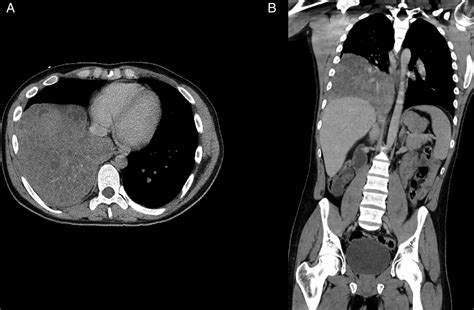

Diagnosing Congenital Pulmonary Airway Malformations (Cpam) typically involves a combination of prenatal and postnatal evaluations. Prenatal diagnosis is often made through ultrasound or magnetic resonance imaging (MRI), which can detect abnormalities in the fetal lungs. Postnatal diagnosis may involve chest X-rays, computed tomography (CT) scans, or MRI to confirm the presence and type of Cpam.

Cpam stands for Congenital Pulmonary Airway Malformation. This term refers to a group of rare congenital lung malformations that affect the development of the lungs and airways. These malformations can vary in severity and presentation, making them a complex area of study for medical professionals.